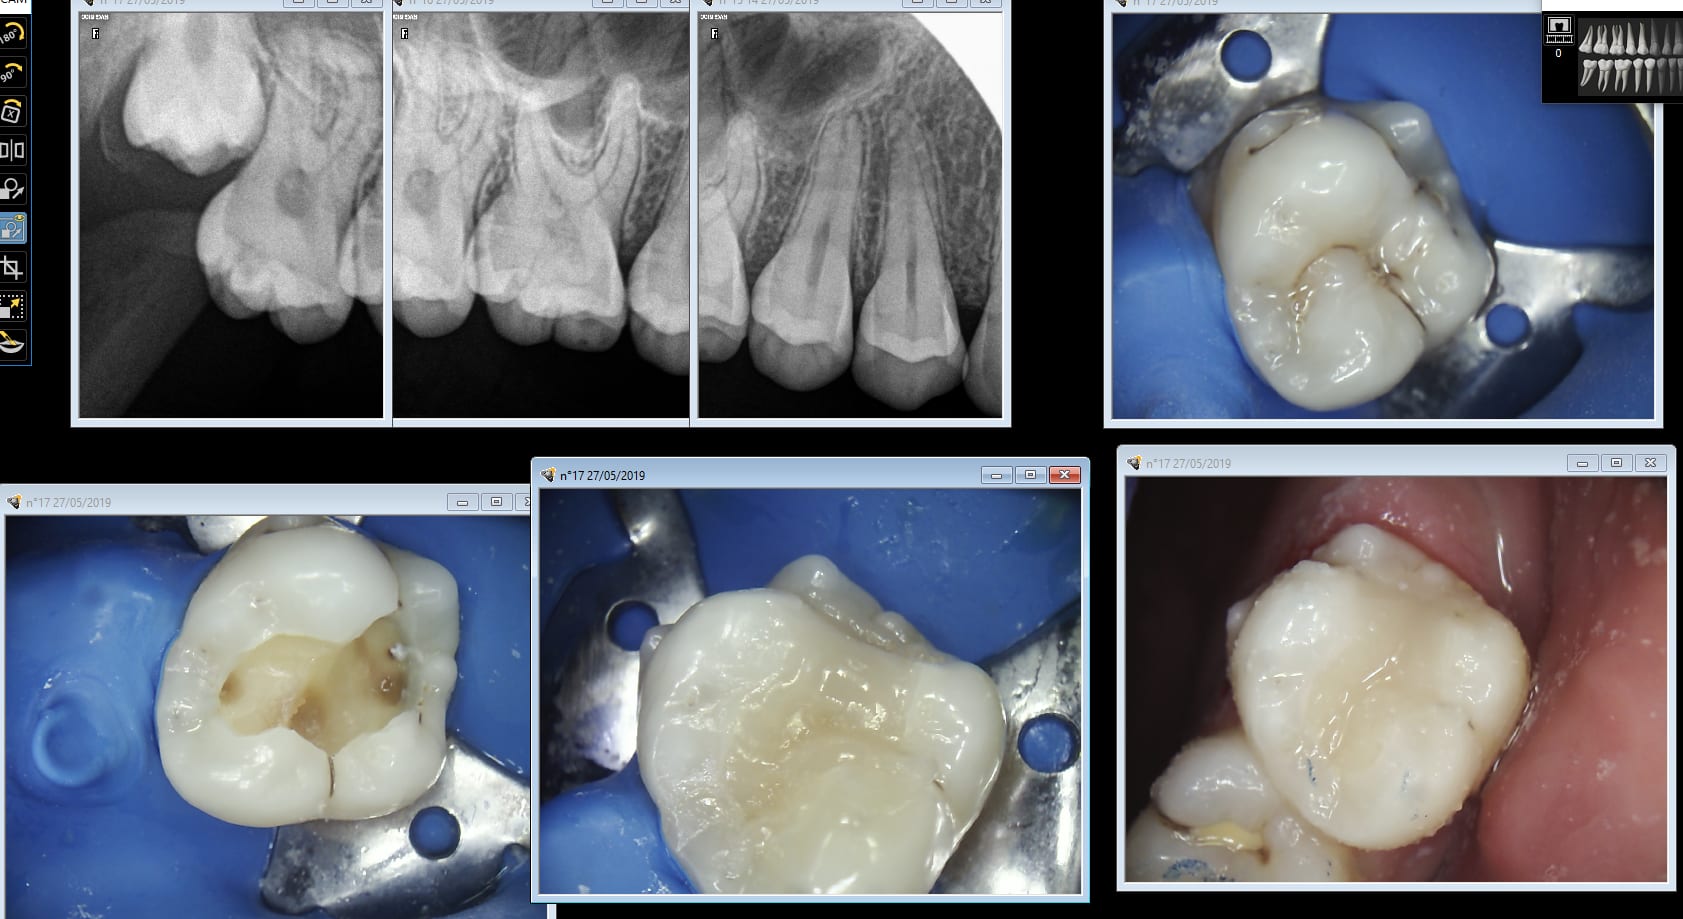

Puisque le sujet a été évoqué récemment, je relance, du matin.

J'en avais une autre prévue mais la crête a pété lors de l'éviction carieuse, pas grave mais du coup je ne pouvais pas présenter de photos.

Preuve donc que ce n'est pas si compliqué.

24 tunnel zedm1z - Eugenol

Img 4409 nlhvso - Eugenol

Img 4410 cw8ykh - Eugenol

Img 4411 cnu7fb - Eugenol